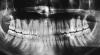

Lebensgefahr Опубликовано 16 августа, 2011 Поделиться Опубликовано 16 августа, 2011 (изменено) Сначала история болезни. Года два назад обратился к одному рекомендованному опытному стоматологу. Жаловался на шестой сверху слева (слева от меня). Не болел, просто обнаружил дырку. Нерв удалять не стали, так запломбировали. Врач обещала повышенную чувствительность, не наврала. Первое время реагировал на что-то твердое, попавшее на жевательную поверхность. Дальше на год я про него забыл. Далее он стал сильно реагировать на холодное и горячее но тут же проходил. Пару дней назад начал ныть, еще через день скрутило так, что кошки стали мне завидовать в навыке стенолазания.Опять по рекомендации поехал в МГМСУ. Фамилию врача пока оглашать не буду.Сделал снимок, стали вскрывать. Далее со слов врача, нерва там уже не было, он сгнил почти полностью во всех трех каналах. Огрызок он удалил без умершвления, после остановки кровотечения сделали еще один снимок с иглами в каналах. Далее самое интересно. После промывки и прочистки каналов он стал пломбировать их гутаперчей. И тут весь приятный образ, созданный им, был испорчен. Он брал на кончик какого-то стоматологического инструмента эту самую резинку и ПЛАВИЛ ЗАЖИГАЛКОЙ. На что я ему резонно заметил, что вы нарушаете технологический процесс. Он ответил "да бросьте вы". Основы российского раздолбайства в МГМСУ наверное преподают тоже.Это напомнило кадры из передачи про индию где зубы лечили прямо на улице, делали не то вставную челюсть не то протезы из эпоксидной смолы.Выскажетесь, пожалуйста, по снимкам и по использованию зажигалки. Если это недопустимо вообще никак стоит ли заставить переделывать?Снимки прилагаю, извините, что плохого качества. Не знаю как их лучше оцифровать. Картинки две одинаковых, одну чуть осветлил, может быть так лучше будет.Еще вопрос вызвавший разногласия в ряду двух стоматологов из разных клиник. ОДин говорит что 6 зуб в гайморовой пазухе, другой говорит что 4 и 5. Кто прав? Изменено 16 августа, 2011 пользователем Lebensgefahr Ссылка на комментарий

Мартовский Опубликовано 16 августа, 2011 Поделиться Опубликовано 16 августа, 2011 Вы врачу либо доверяете, либо нет. Какой смысл идти снова, если что-то не так? На снимках у вас зуб до лечения, и с местер-штифтами, там комментировать нечего. Про зажигалку - у нас на кафедрах врачи много чего придумывают, не от жиру понятно. Ссылка на комментарий

Lebensgefahr Опубликовано 18 августа, 2011 Автор Поделиться Опубликовано 18 августа, 2011 (изменено) Закончил врач с 6 сверху слева. Выскажите, пожалуйста, свое мнение.Еще очень интересно услышать про 6 снизу слева.Удалял нерв году в 93-95. По мнению двух врачей каналы запломбированы резорцин-формалиновой пастой. Цвет зуба (с их слов) розовый. Не беспокоит. Жевательная поверхность уже сильно износилась, хотел подправить. ОДин врач говорит, нужно распломбировывать каналы и т.д. Второй сказал не трогать, делать снимки, "смотреть в динамике". Или одеть коронку.Прицельный шестого снизу есть, но что-то сканер нормально не берет. ФОтоаппаратом пробовал, еще хуже.Прицельного сверху нет, решил что проще сделать все сразу :-) Изменено 18 августа, 2011 пользователем Lebensgefahr Ссылка на комментарий

shishok Опубликовано 18 августа, 2011 Поделиться Опубликовано 18 августа, 2011 К сожалению 6 снизу не получился(верхушки корней в "тени") Ссылка на комментарий